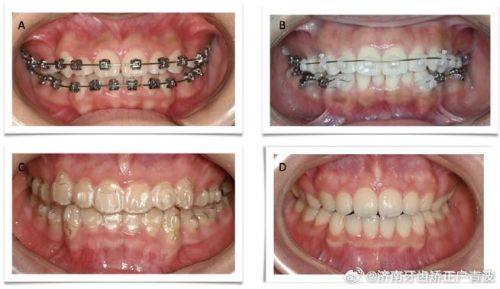

错合畸形正畸治疗:可开展青少年及成人各类错合畸形唇侧正畸、无托槽隐形矫正,同时支持儿童早期干预正畸,兼顾矫正成效与口腔美学,适配不同患者的需求。